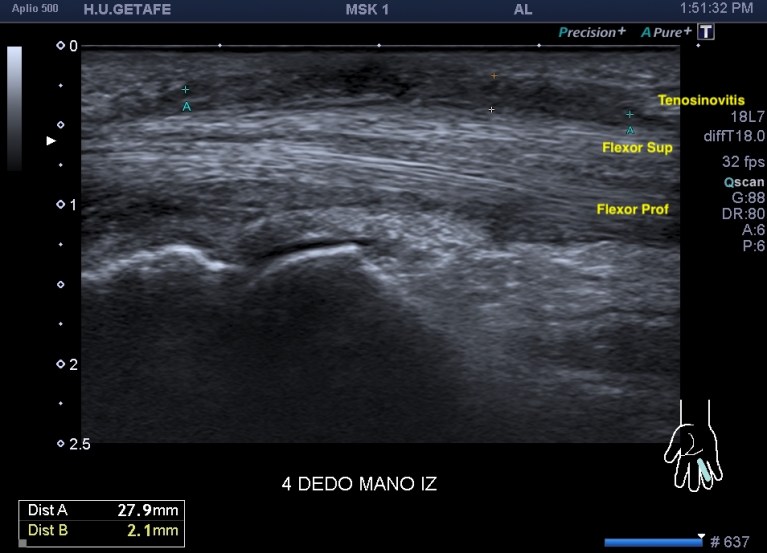

En la imagen 1 puedes ver la relación en eje largo de los flexores del 4 dedo con la tenosinovitis que de modo superficial está afectando al tendón, como una banda hipoecogénica, como si fuera una boina. Es la responsable de la falta de movilidad del dedo en la dinámica.